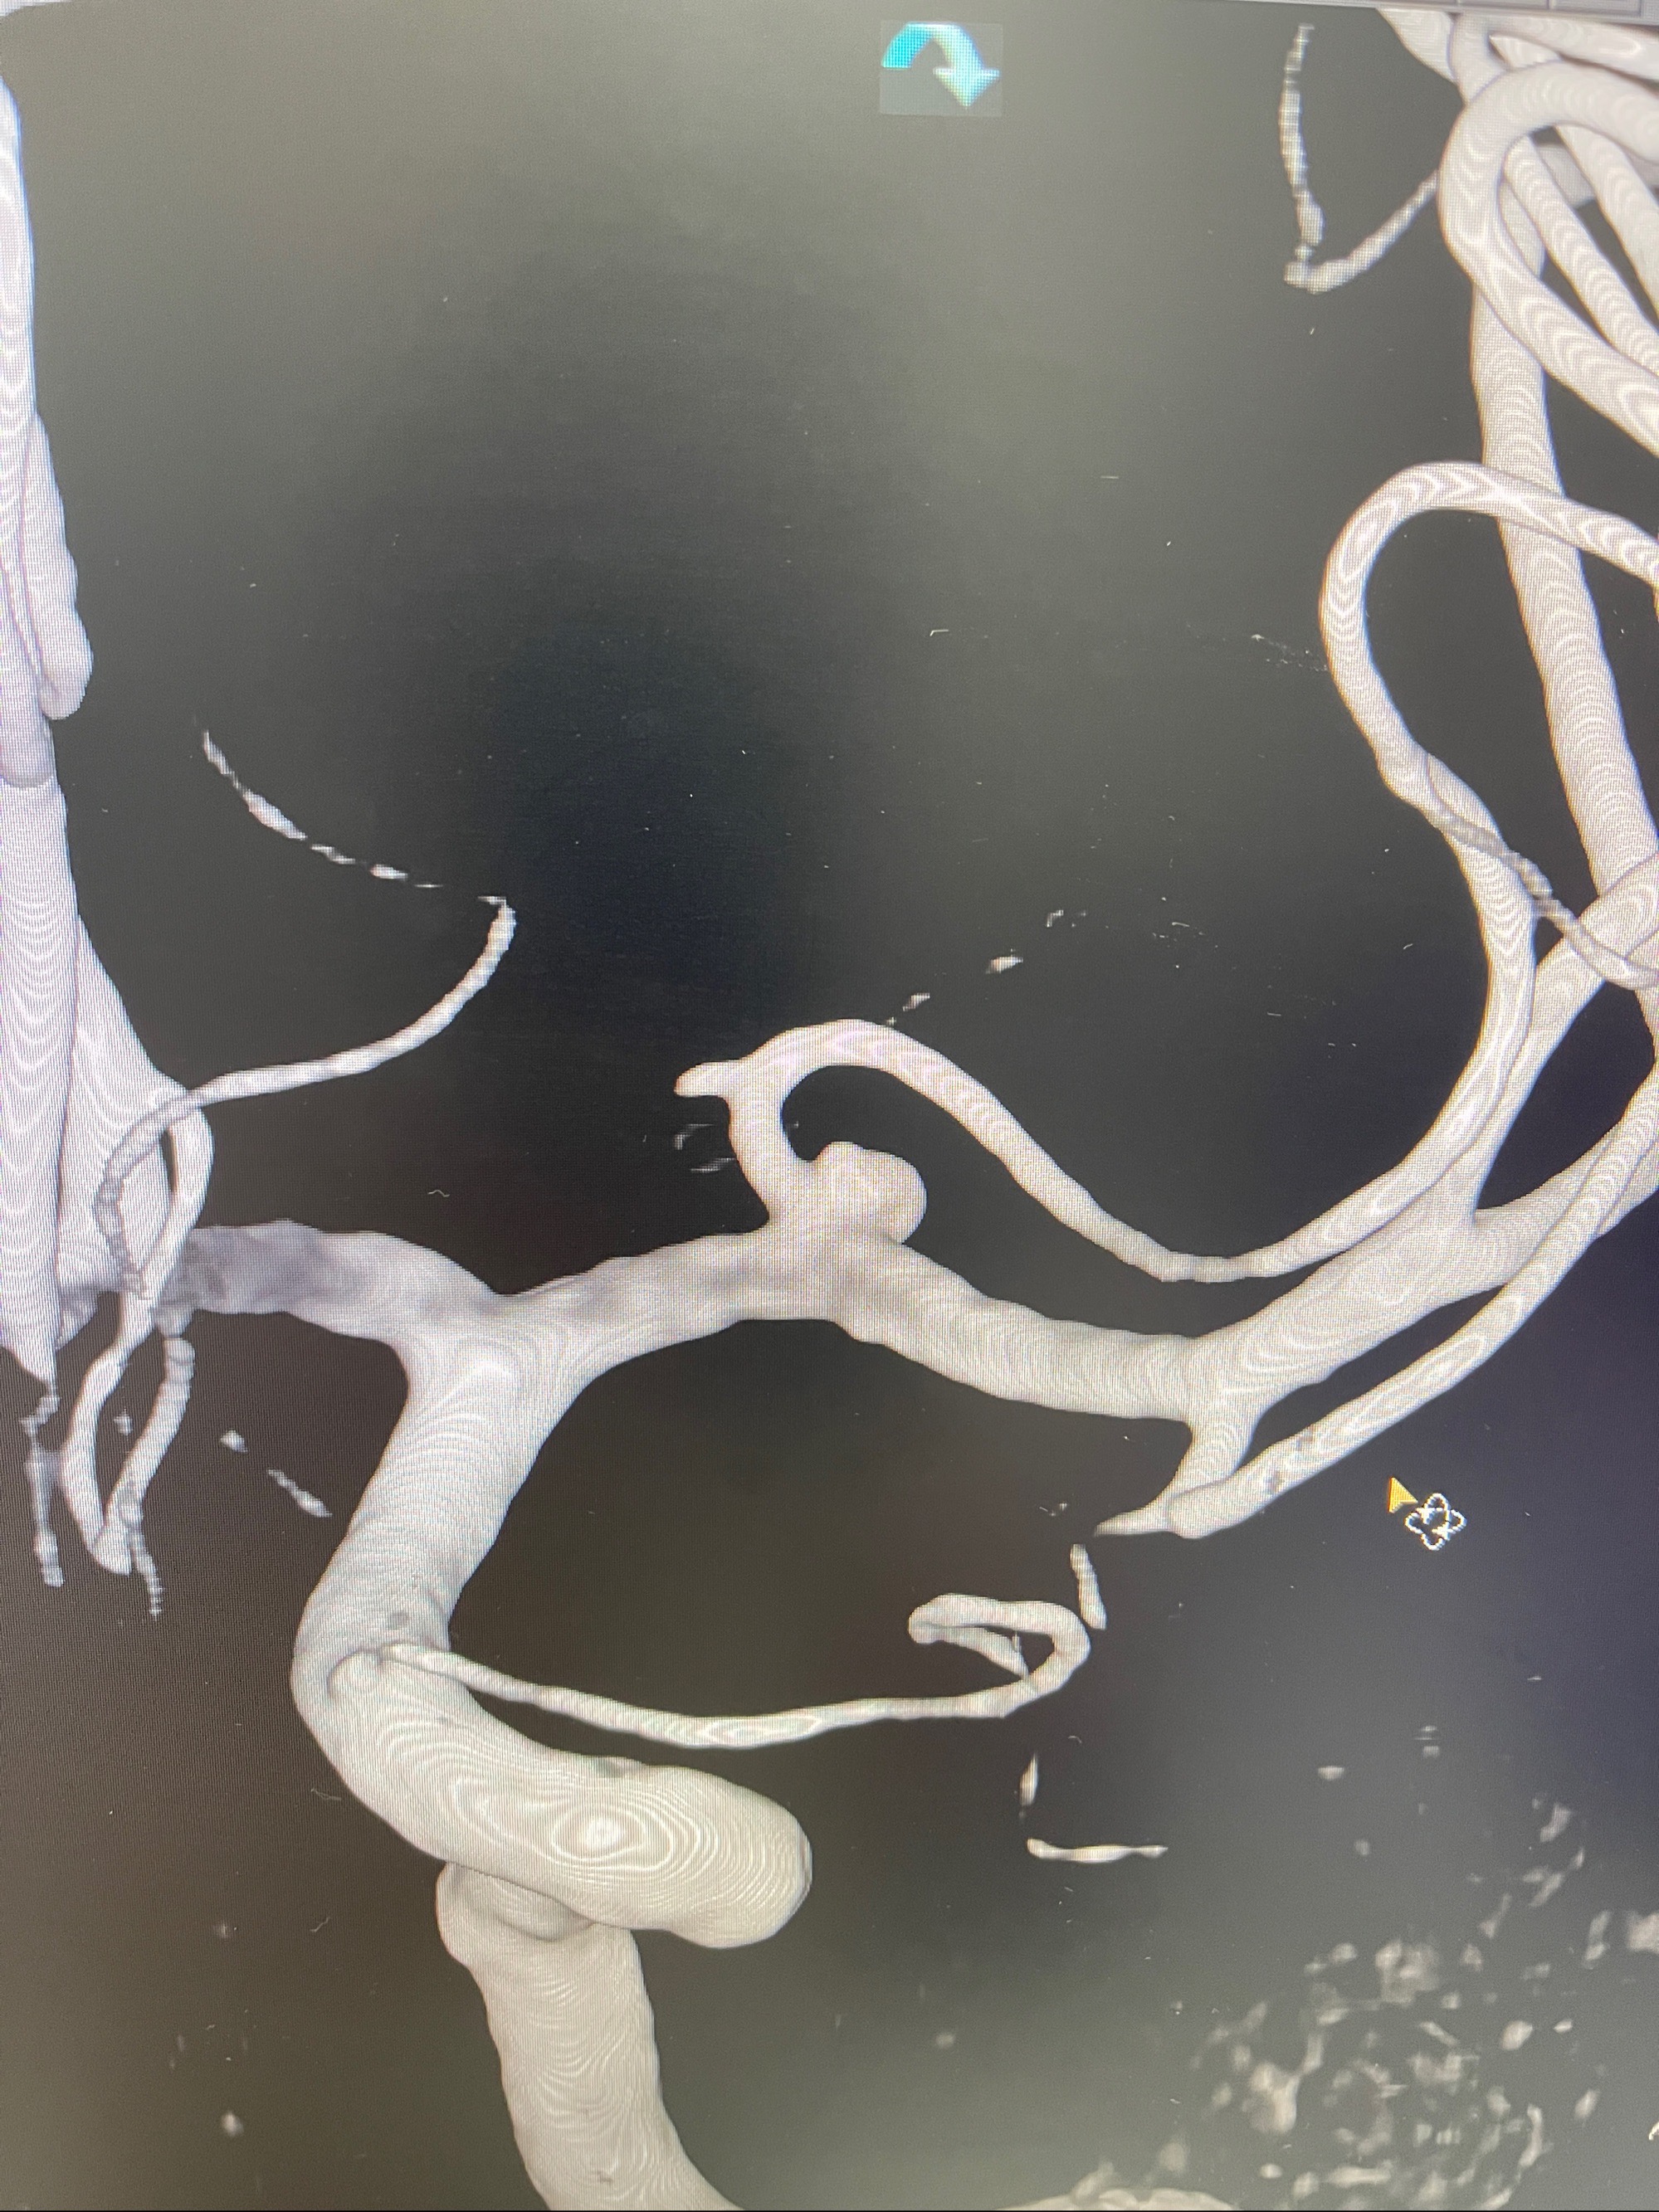

左侧大脑中动脉动脉瘤,约2.6-2.8-3.4-2mm大小(瘤颈部、瘤体部、瘤高)

1.左侧大脑中动脉动脉瘤,约2.6-2.8-3.4-2mm大小(瘤颈部、瘤体部、瘤高)